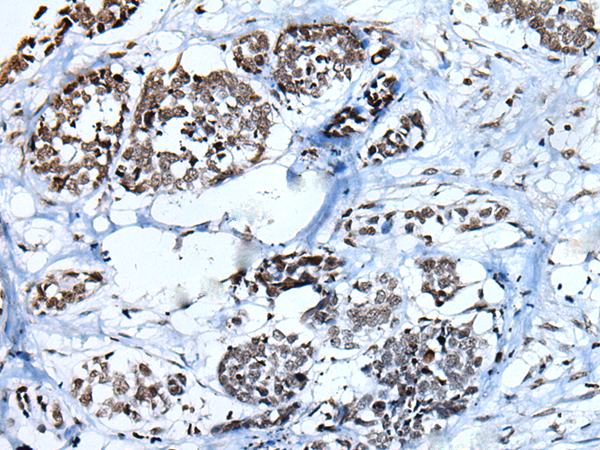

IHC positive control:

Human liver cancer

IHC Recommend dilution:

25-100